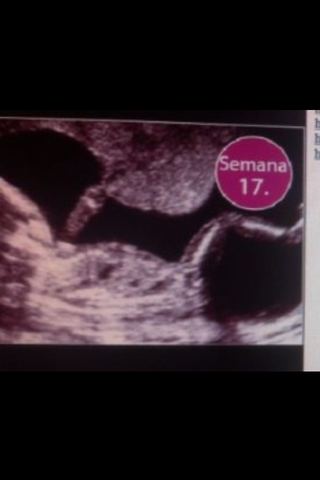

Sus brazos se alargan y a sus piernas aun les falta desarrollarse

Les aparece en todo el cuerpo lanugo

Su cuello se alarga

Sus músculos se empiezan a ejercitar

Los brazos y piernas ya están más proporcionados

El cerebro controla sus movimientos